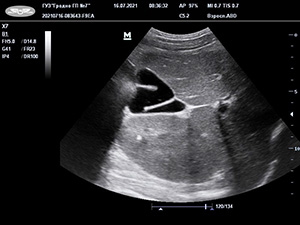

Застой желчи, или билиарный сладж, у детей визуализируется в виде взвеси гиперэхогенных частиц; другие варианты крайне редки. Конкременты выявляются независимо от возраста (даже у пациентов до 3 лет).

Рисунок. S-образные формы желчного пузыря. Результаты УЗИ.